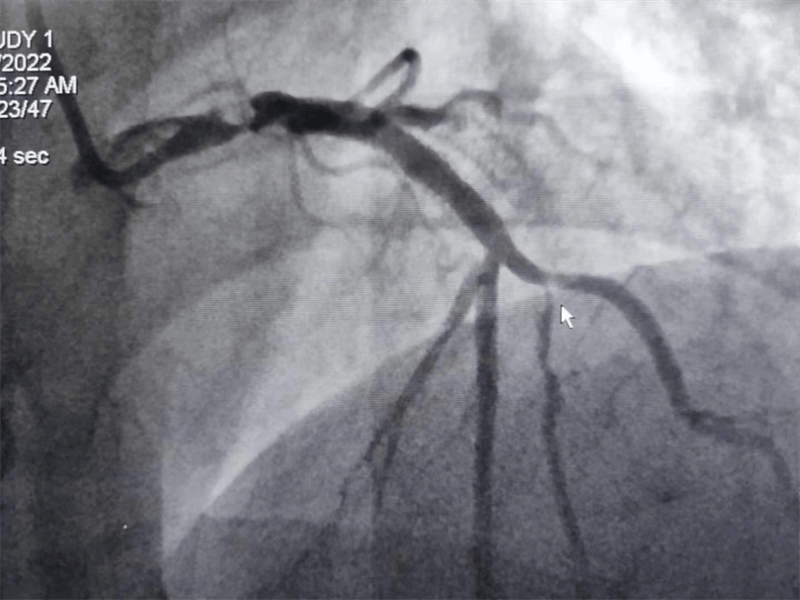

挽救患者生命,挽救一個(gè)家庭的希望!當(dāng)導(dǎo)絲通過(guò)病變區(qū)域時(shí),大家的心都緊張了起來(lái),經(jīng)過(guò)精細(xì)、快速的操作,手術(shù)順利完成,原來(lái)像頭發(fā)絲一樣粗細(xì)的“血路”,終于恢復(fù)了正常!

我們結(jié)合患者病變特點(diǎn),對(duì)回旋支支架內(nèi)閉塞病變處藥物球囊治療,左主干病變植入1枚支架,術(shù)后,造影顯示左主干病變處支架植入狀態(tài)良好,血管內(nèi)超聲顯示支架貼壁良好,患者血壓、心率穩(wěn)定,癥狀完全緩解,并安全返回重癥監(jiān)護(hù)室進(jìn)一步治療,術(shù)后張大伯無(wú)明顯不適,生命體征穩(wěn)定,病情明顯好轉(zhuǎn)。